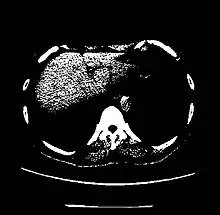

CT scan of the thorax with window level set to 60 HU (liver)

Liver 60 ± 6[23]